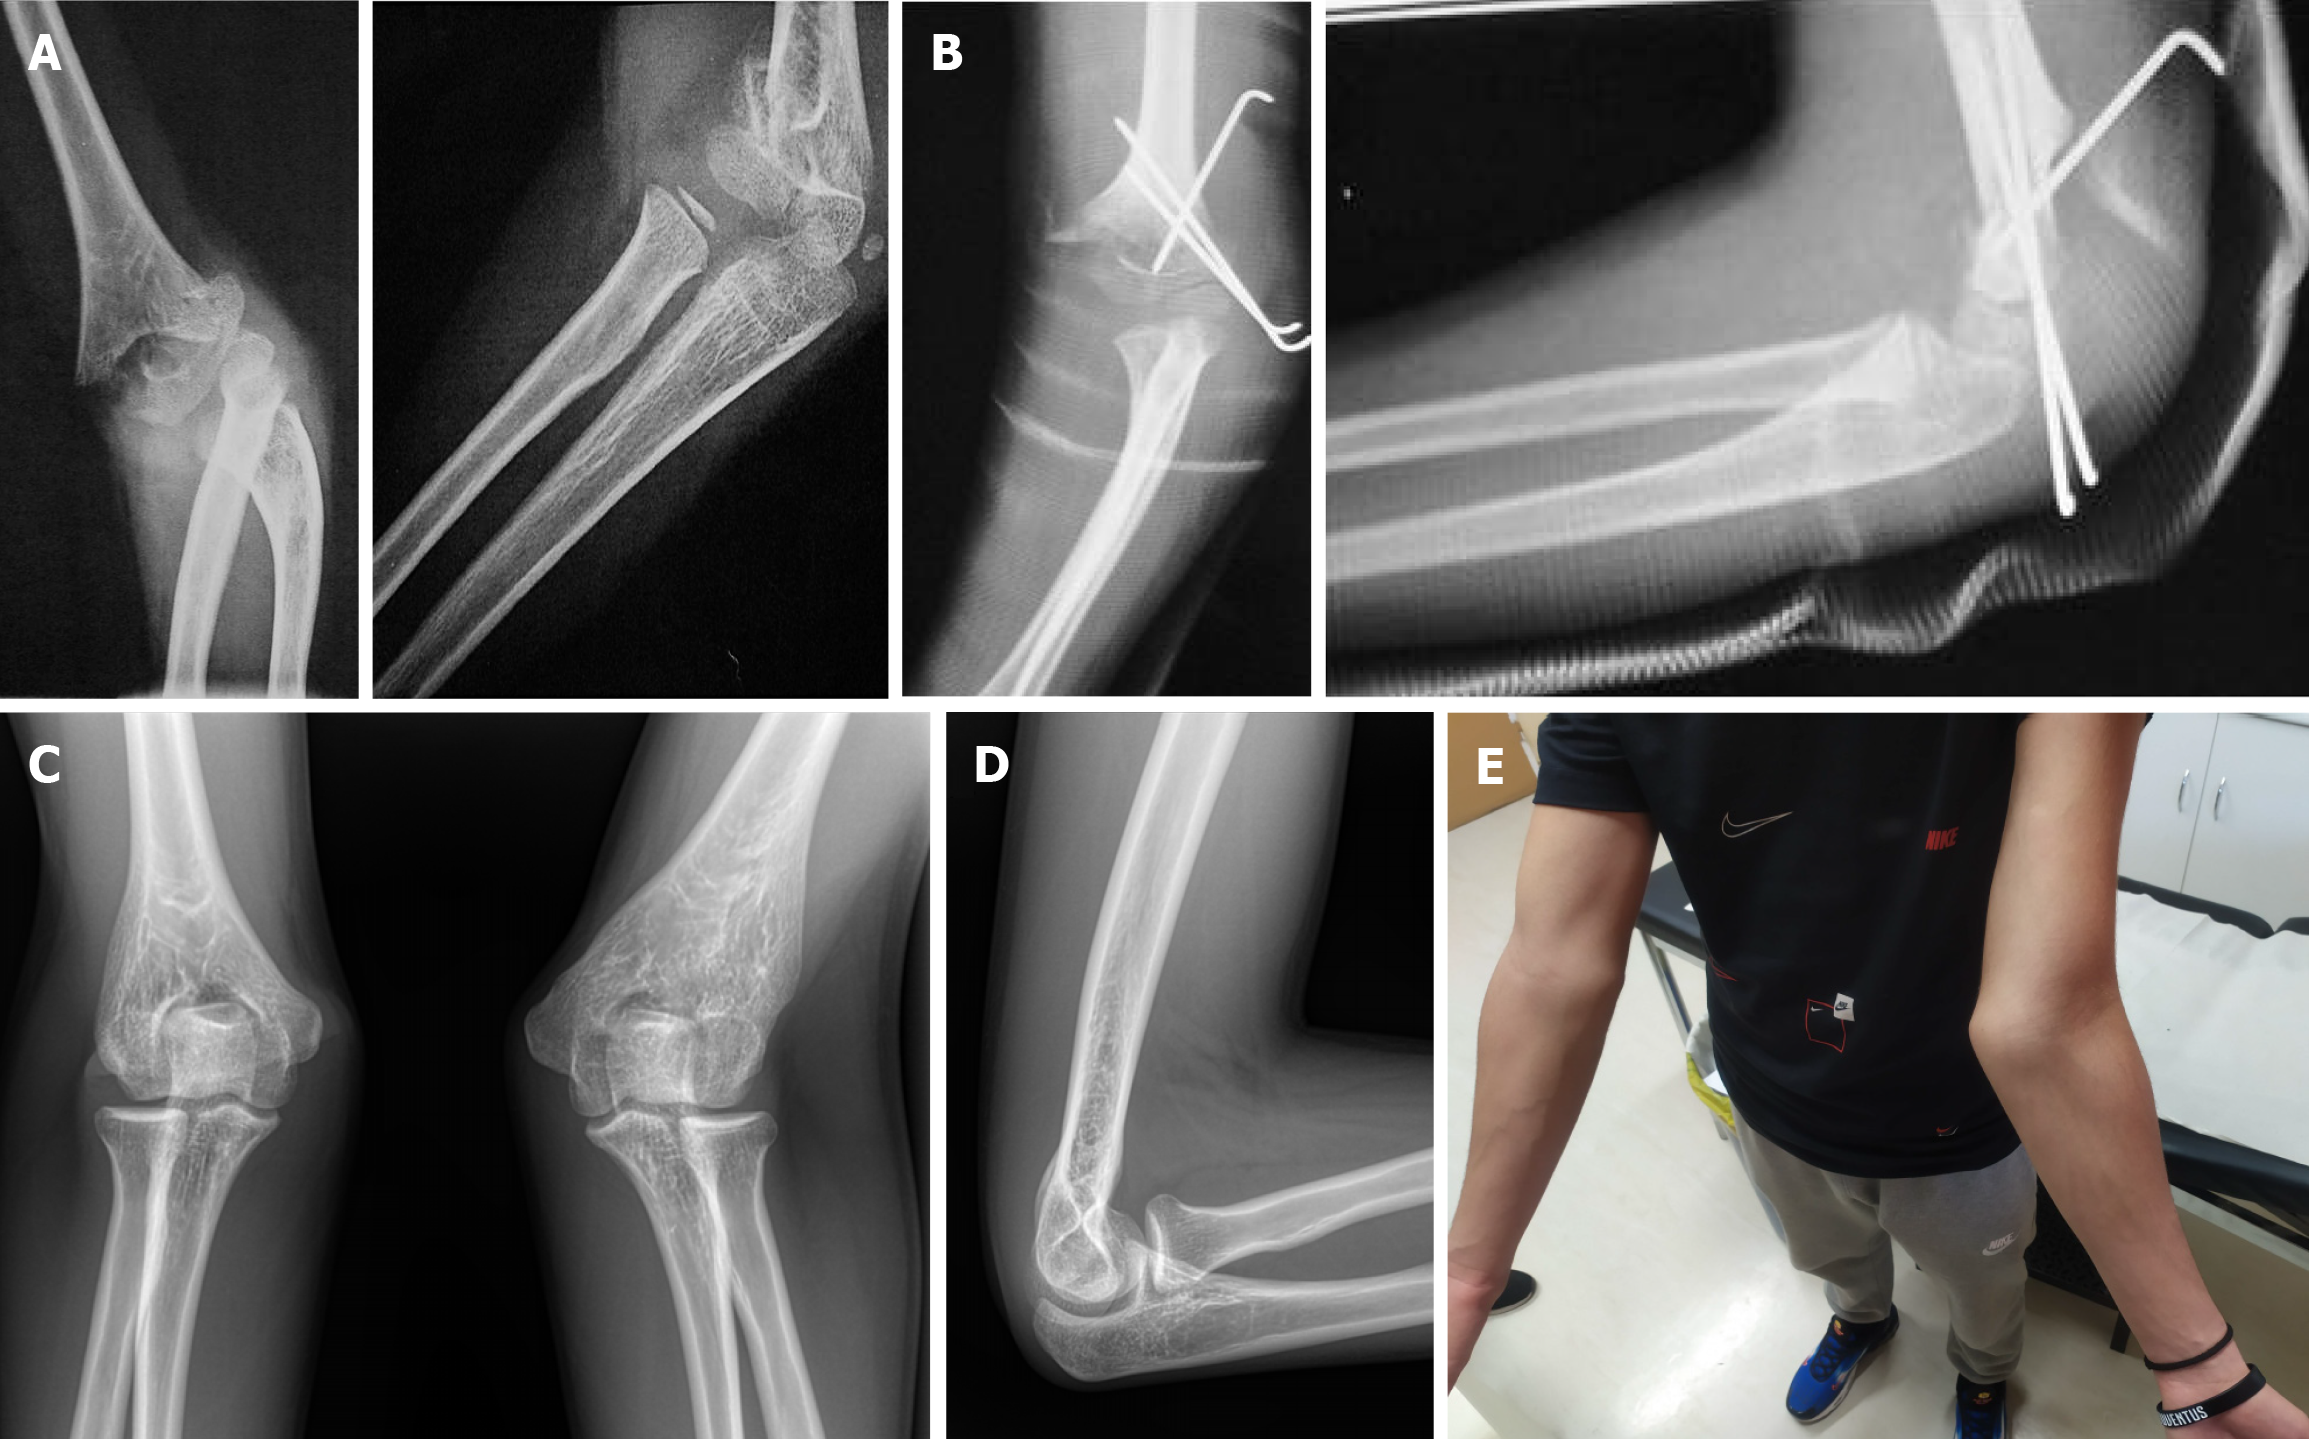

Figure 3 Malrotation can be easily missed, and it is poorly corrected by remodeling.

A: A 10-year-old male with a Gartland III supracondylar humeral fracture with marked internal rotation of the condyles; B: Despite open reduction and both column pinning, residual rotational deformity can be noticed by cortex mismatching in anteroposterior and lateral X-rays (orange arrows indicate cortex discontinuity); C: X-rays in 3 months follow-up with satisfactory functional outcome.